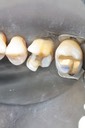

Mark Chun #14-15 model

Mark Chun #14-15 finish